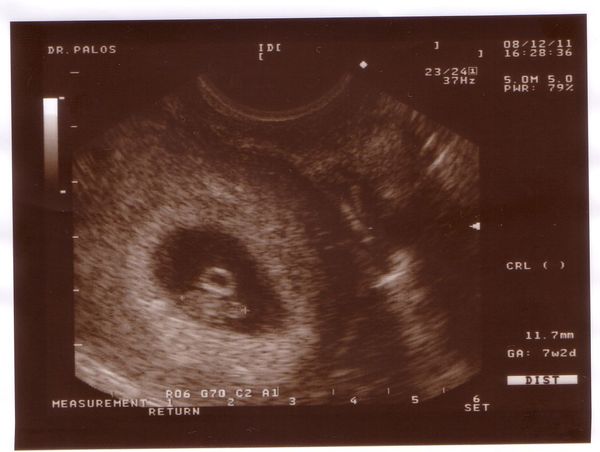

Sziasztok, én is láttam Őt. 7 hetes 2 napos vok, és vert a szivecskéje. Kicsordult a könnyem örömömben. 11,7 mm a kis babócám.Legközelebb 2008.12.30-án megyek.